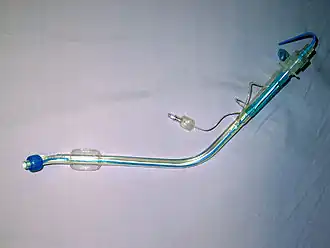

A tracheal tube is a catheter that is inserted into the trachea for the primary purpose of establishing and maintaining a patent (open and unobstructed) airway. Tracheal tubes are frequently used for airway management in the settings of general anesthesia, critical care, mechanical ventilation, and emergency medicine. Many different types of tracheal tubes are available, suited for different specific applications. An endotracheal tube is a specific type of tracheal tube that is nearly always inserted through the mouth (orotracheal) or nose (nasotracheal). It is a breathing conduit designed to be placed into the airway of critically injured, ill or anesthetized patients in order to perform mechanical positive pressure ventilation of the lungs and to prevent the possibility of aspiration or airway obstruction.[25] The endotracheal tube has a fitting designed to be connected to a source of pressurized gas such as oxygen. At the other end is an orifice through which such gases are directed into the lungs and may also include a balloon (referred to as a cuff). The tip of the endotracheal tube is positioned above the carina (before the trachea divides to each lung) and sealed within the trachea so that the lungs can be ventilated equally.[25] A tracheostomy tube is another type of tracheal tube; this 50–75-millimetre-long (2.0–3.0 in) curved metal or plastic tube is inserted into a tracheostomy stoma or a cricothyrotomy incision.[26]

Originally made from latex rubber,[30] most modern endotracheal tubes today are constructed of polyvinyl chloride. Tubes constructed of silicone rubber, wire-reinforced silicone rubber or stainless steel are also available for special applications. For human use, tubes range in size from 2 to 10.5 mm (0.1 to 0.4 in) in internal diameter. The size is chosen based on the patient's body size, with the smaller sizes being used for infants and children. Most endotracheal tubes have an inflatable cuff to seal the tracheobronchial tree against leakage of respiratory gases and pulmonary aspiration of gastric contents, blood, secretions, and other fluids. Uncuffed tubes are also available, though their use is limited mostly to children (in small children, the cricoid cartilage is the narrowest portion of the airway and usually provides an adequate seal for mechanical ventilation).[13]

In addition to cuffed or uncuffed, preformed endotracheal tubes are also available. The oral and nasal RAE tubes (named after the inventors Ring, Adair and Elwyn) are the most widely used of the preformed tubes.[31]